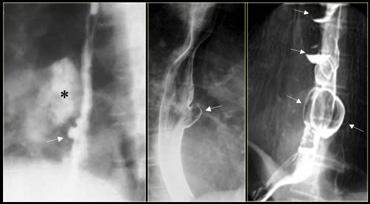

Bên trái là các túi thừa cửa sổ chủ-phổi nhỏ (mũi tên), là phát hiện tình cờ ở hai bệnh nhân.

Ngoài cùng bên trái là túi thừa do kéo (mũi tên) do bệnh u hạt vùng rốn phổi.

Hạch vôi hóa (dấu hoa thị).

Ở giữa là túi thừa do áp lực (mũi tên) do tăng áp lực trong lòng ống.

Bên phải là nhiều túi thừa do áp lực (mũi tên) xuất hiện trước khi thực hiện phẫu thuật cắt cơ Heller điều trị co thắt tâm vị (achalasia).

Bên trái là túi thừa do kéo (mũi tên) thứ phát sau lao hậu nguyên phát.

Hình ảnh này có thể nhầm lẫn với tổn thương phổi dạng hang trên phim X-quang ngực.